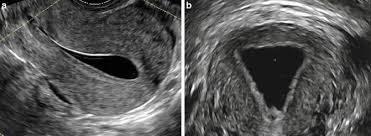

Normal Cavity

Septate vs bicornuate- septum vs bicornuate may be difficult to distinguish on HSG- recommend MRI or 3D US. Examples

- The cavity fills with a small triangular shaped indent of the fundus, suggestive of arcuate uterus vs septum

- The cavity fills as two symmetric horns, suggestive of septate vs bicornuate uterus

- The cavity fills as two distinct, closely approximated symmetric uterine horns, suggestive of septum. Cannot r/o bicornuate.

- The cavity fills as two distinct, symmetric divergent uterine horns. The angle between is suggestive of a bicornuate uterus.

- (A) Normal uterus; (B) Arcuate uterus; (C, D)Bicornuate uterus; (E, F, G) Partial septate uterus; (H) Complete septate